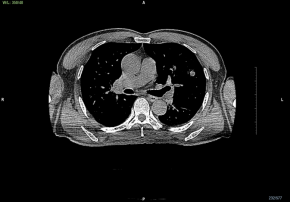

尽管结节比一颗花生大不了多少,但凭借团队医生高超的技术,以及呼吸内镜中心导航系统及DSA的加持,穿刺针穿过管壁,顺利找到了病灶,为了多维度保证位置的准确,介入团队此次利用高大上的锥形束CT进行术中实时定位,确保万无一失。

为避免患者二次手术,术前已获取患者知情同意并签字。 当病理确认后,陈恩国介入团队拔出活检钳,置入Broncus最新研发的二代射频消融系统对肺癌进行消融治疗。该系统为肺部专用射频消融系统,通过盐水灌注系统充分保证消融效率与安全,具有温度可控、过热保护、操作时间短、可重复性强等优点,全程射频温度控制在60-80℃,保证消融安全和有效。

术中阻抗和温度曲线非常平稳,手术顺利